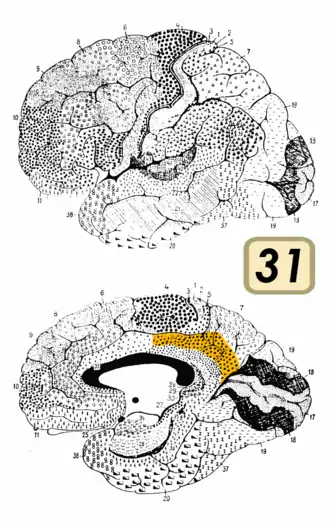

Brodmann area 31

Medial surface of the human brain. BA31 is shown in red. | |

Brodmann area 31, also known as dorsal posterior cingulate area 31, is a subdivision of the cytoarchitecturally defined cingulate region of the cerebral cortex.[1] In the human, it occupies portions of the posterior cingulate gyrus and medial aspect of the parietal lobe. Approximate boundaries are the cingulate sulcus dorsally and the parieto-occipital sulcus caudally. It partially surrounds the subparietal sulcus, the ventral continuation of the cingulate sulcus in the parietal lobe. Cytoarchitecturally it is bounded rostrally by the ventral anterior cingulate area 24, ventrally by the ventral posterior cingulate area 23, dorsally by the gigantopyramidal area 4 and preparietal area 5 and caudally by the superior parietal area 7 (H) (Brodmann-1909).